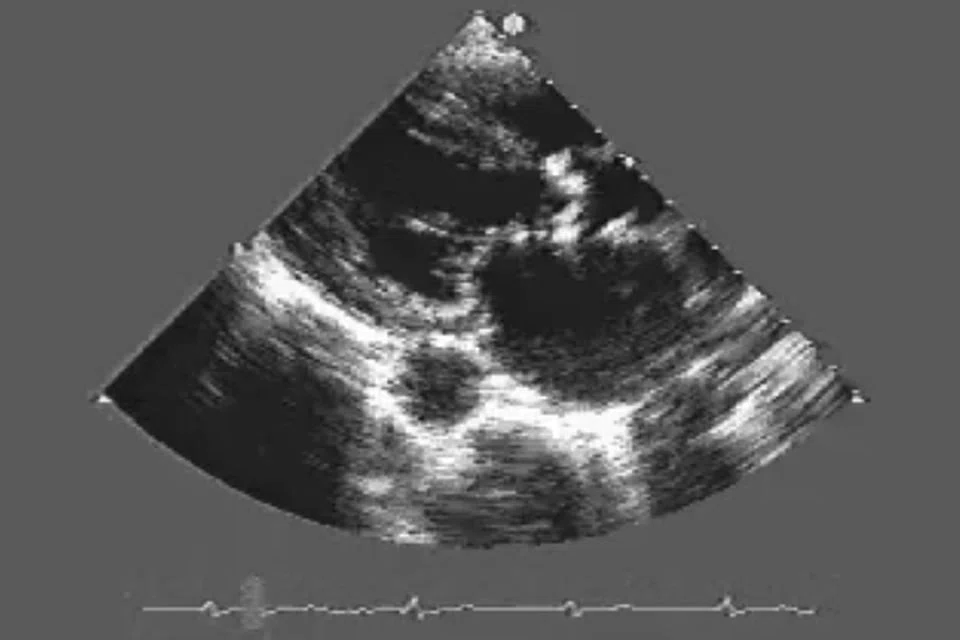

Heart failure and its aetiology can be assessed by echocardiogram, magnetic resonance imaging of the heart and radionuclide myocardial perfusion imaging. CT coronary angiogram is useful to assess the presence of coronary artery disease non-invasively. Invasive coronary angiography can ultimately assess the presence or absence of significant coronary artery disease.